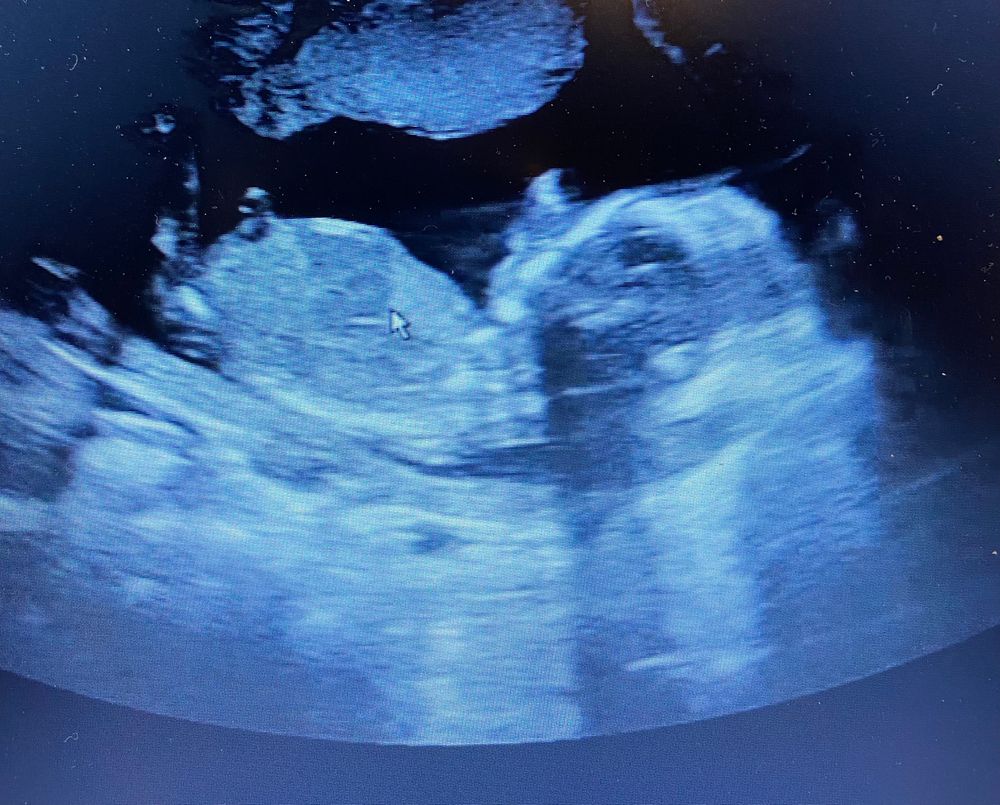

Гадаем пол 🙈

Девочки, всем спасибо за ответы!) у нас девочка 😍

Мальчик, 100%😁

Мальчик

Мальчик)

Ставлю на мальчика

Пацан )

Думаю мальчик. Хотя плохо видно бугорок

Думаю, что мальчик)

У меня при таком же наклоне - мальчик, хотя узист говорил, что девочка 90%

Мальчика вижу 🤔

Просто интересно 🤔😁 Наш пирожок :)) 16 недель